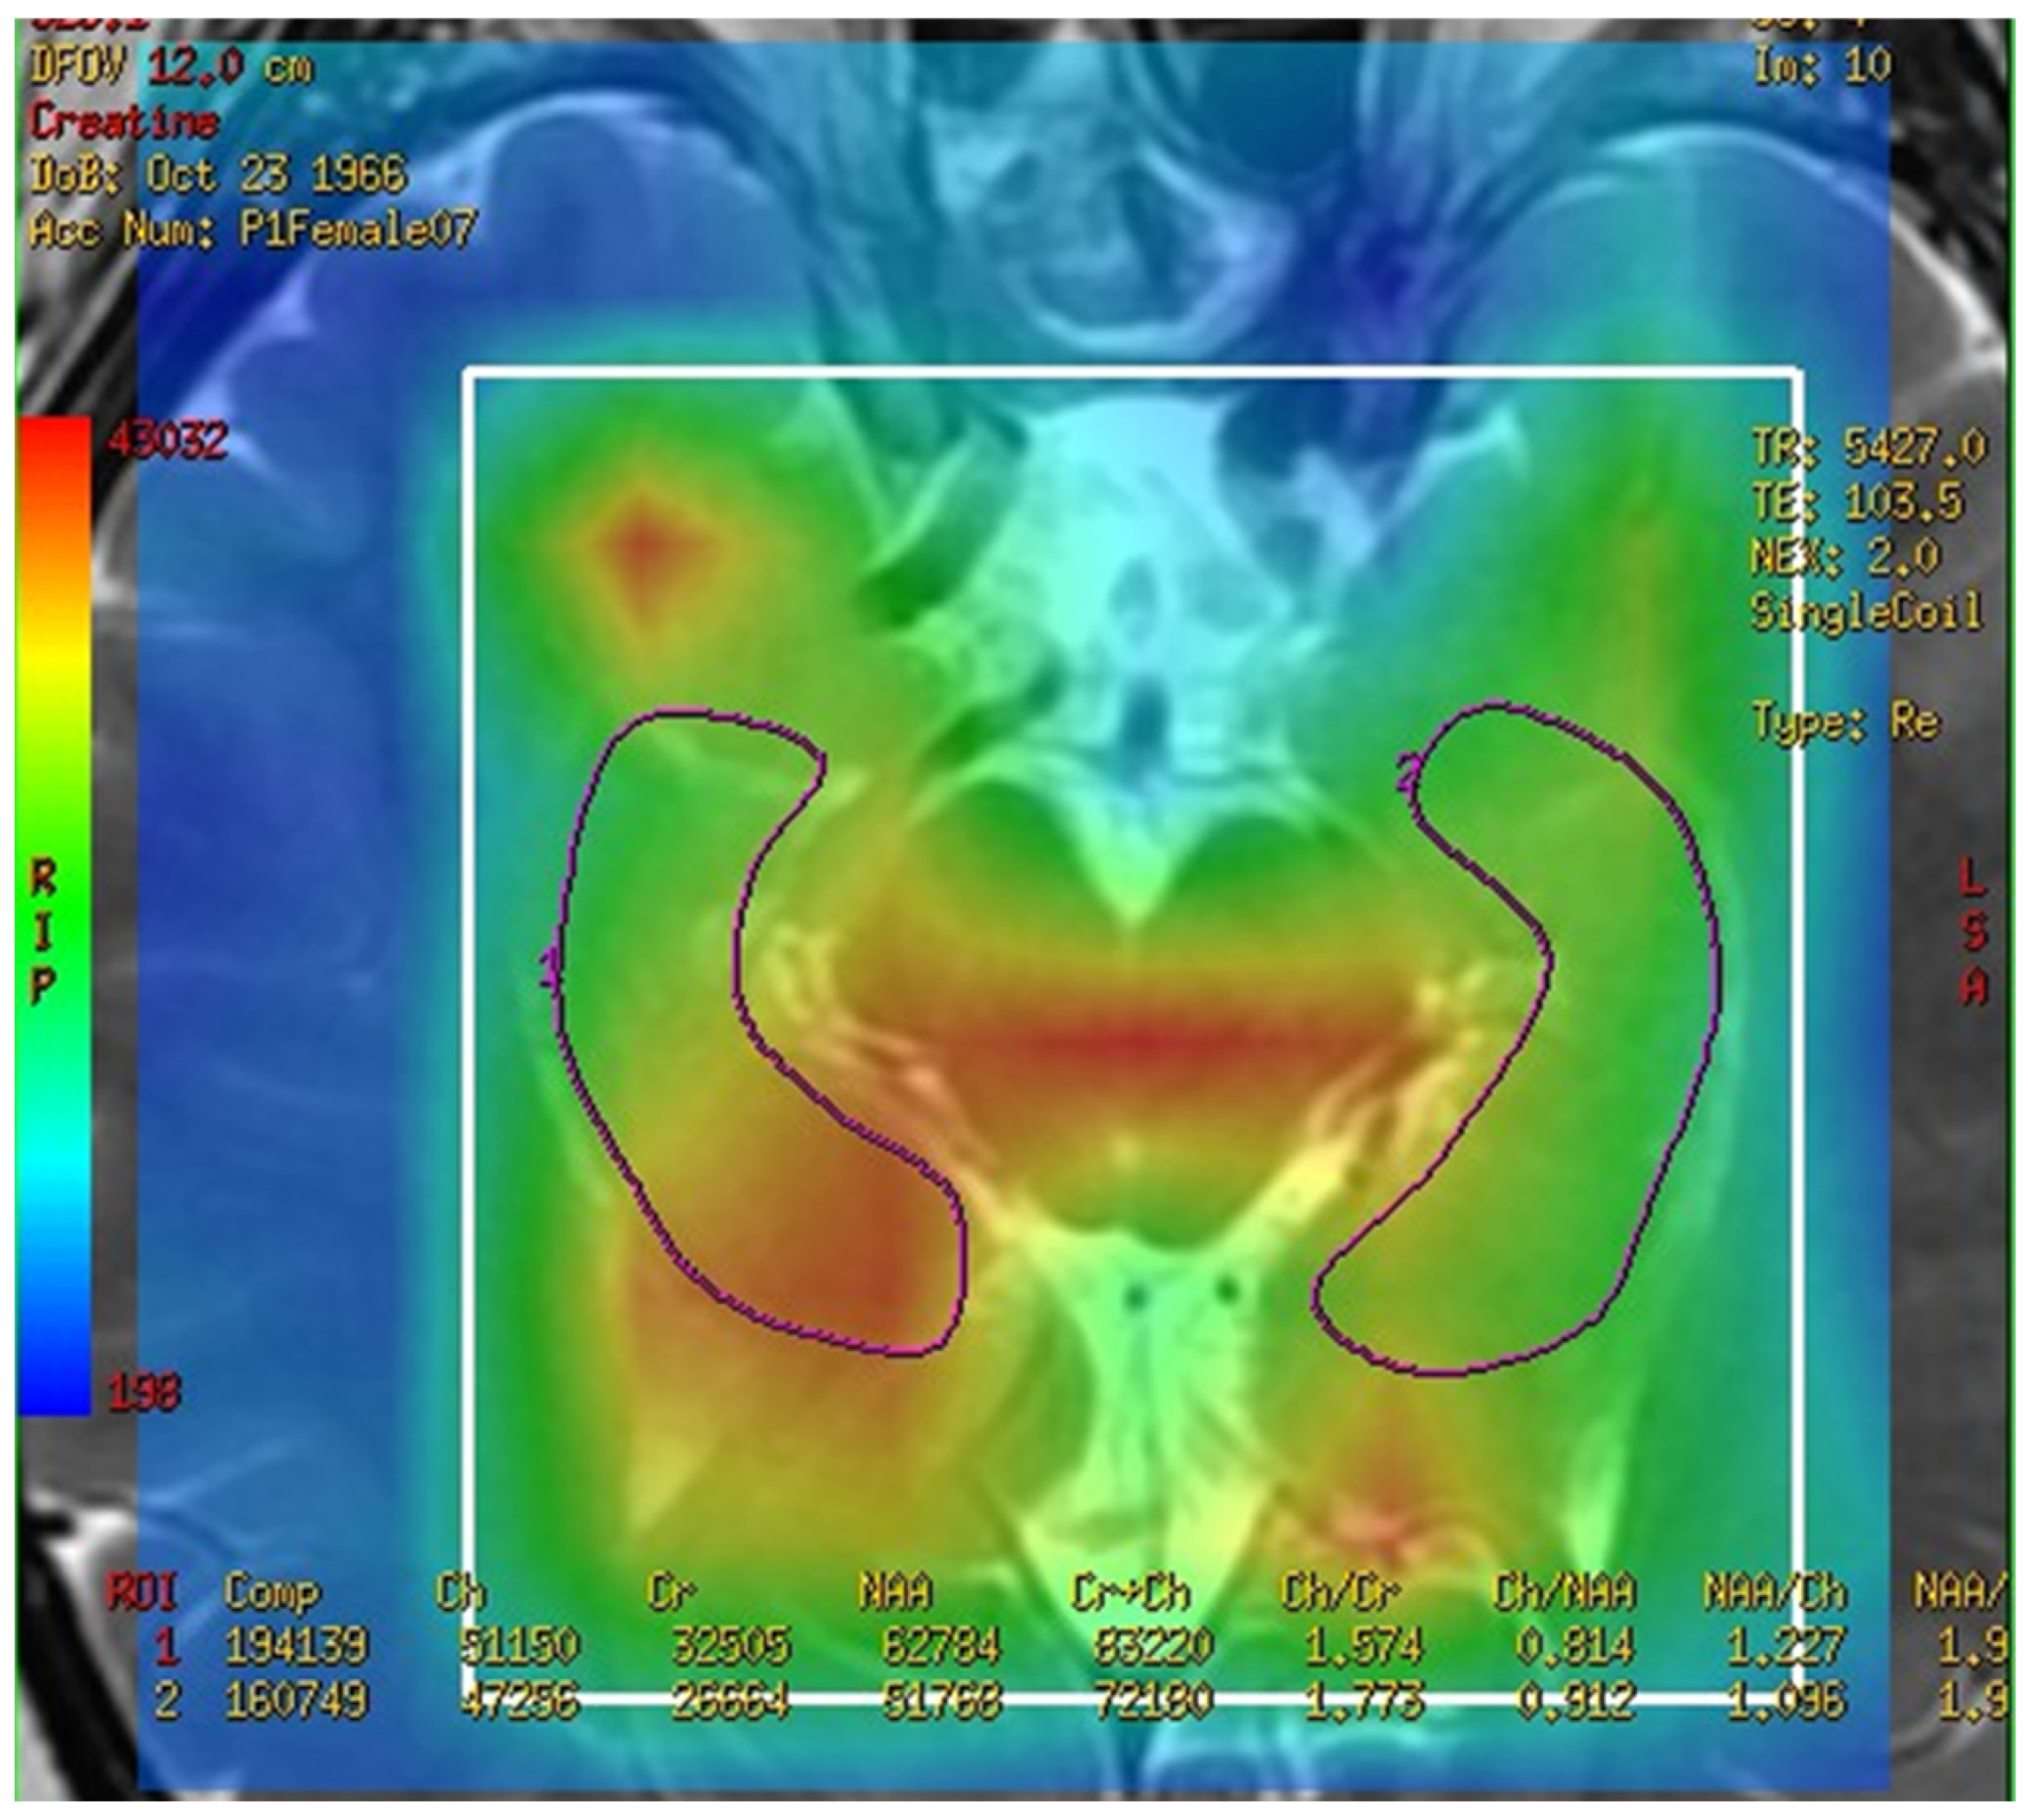

On comparing the metabolites in the corpus callosum between the MCI and control group, the ratio of normal Cr between two groups compared as follows: NAA/Cr (0.778 ± 0.333 vs. 2.506 ± 1.648, p = 0.020), MI/Cr (0.062 ± 0.056 vs. 0.222 ± 0.136), and the level of signal intensities of Cr (4200 ± 2100 vs. 16,200 ± 11,800, p = 0.02) were significantly lower in the MCI group (Table 3). The result was easily visible in the color map of the MRS with 3D-CSI. For example, the MRS with 3D-CSI color map of NAA showed a red color (high signal) in the corpus callosum area of the control group, while it showed a blue color (low signal) in the corpus callosum area of the MCI group (Figure 4). For the levels of signal intensities of Cho/Cr, there was a trend of lower intensity at the corpus callosum in the MCI group compared with the control group, but without significant difference.

Figure 4.

Magnetic resonance spectroscopy with three-dimensional chemical shift images color map of N-acetyl aspartate. The left figure shows red color (high signal intensity) in the corpus callosum area (green markup) of control group. The right figure shows blue color (low signal intensity) in the corpus callosum area (green markup) of mild cognitive impairment group.